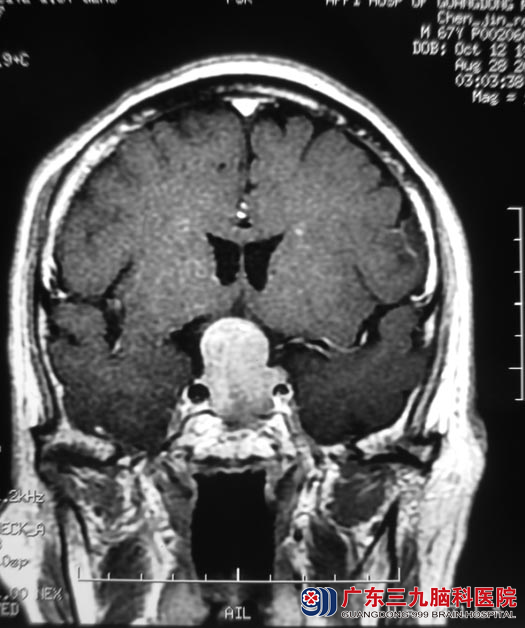

广东三九脑科医院头颅MR显示:鞍区占位性病变,考虑为垂体大腺瘤,约1.6cm×1.5cm×2.8cm;血液检查结果提示:内分泌激素明显增高。http://www.999brain.com/

▲手术前